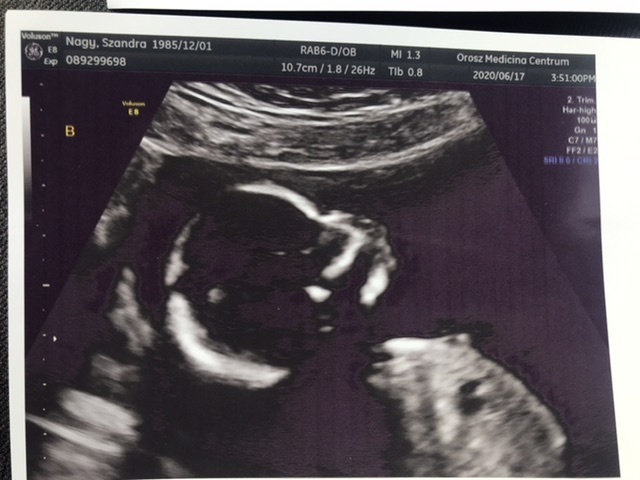

Én hétfőn voltam 12 hetes UH-n 13 hetesen

Szívhang, orrcsont, tarkóredő 1,4 mm, ülőmagassága 63mm. Azt mondta a doki minden rendben,megfelelően fejlődik. Sajnos a férjem nem jöhetett be (nálunk Erdélyben még komoly megszorítások vannak sajnos), viszont a doki adott néhány fotót 3Dt is, hogy mutassam meg a leendő apának. Nagyon cuki volt. A nemét is megtudtuk, 90 százalékban kisfiú a doki szerint, nem volt túl szégyenlős a babóca